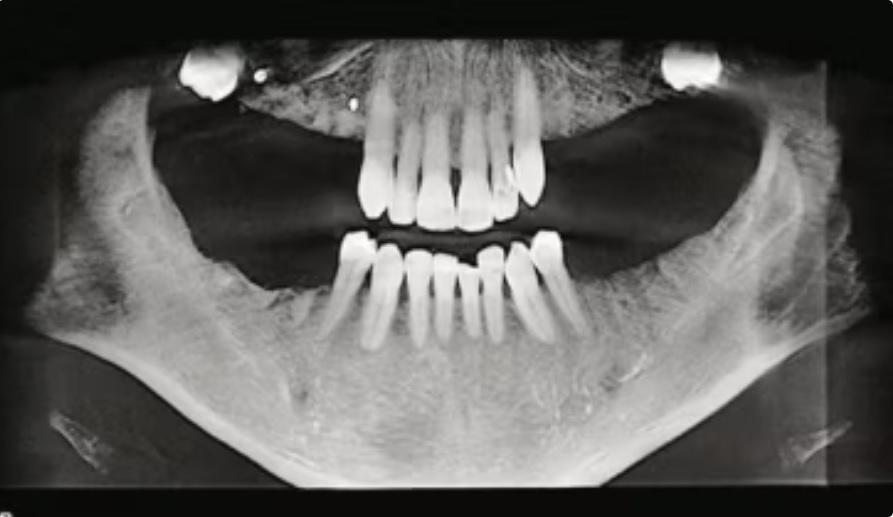

Панорамная рентгенограмма после установки зубных имплантатов и планирования лечения укороченной зубной дуги.

Далее было принято решение об удалении всех оставшихся коренных зубов и премоляров, кроме двух. После пациенту было установлено четыре имплантата, и было запланировано лечение укороченной зубной дуги.